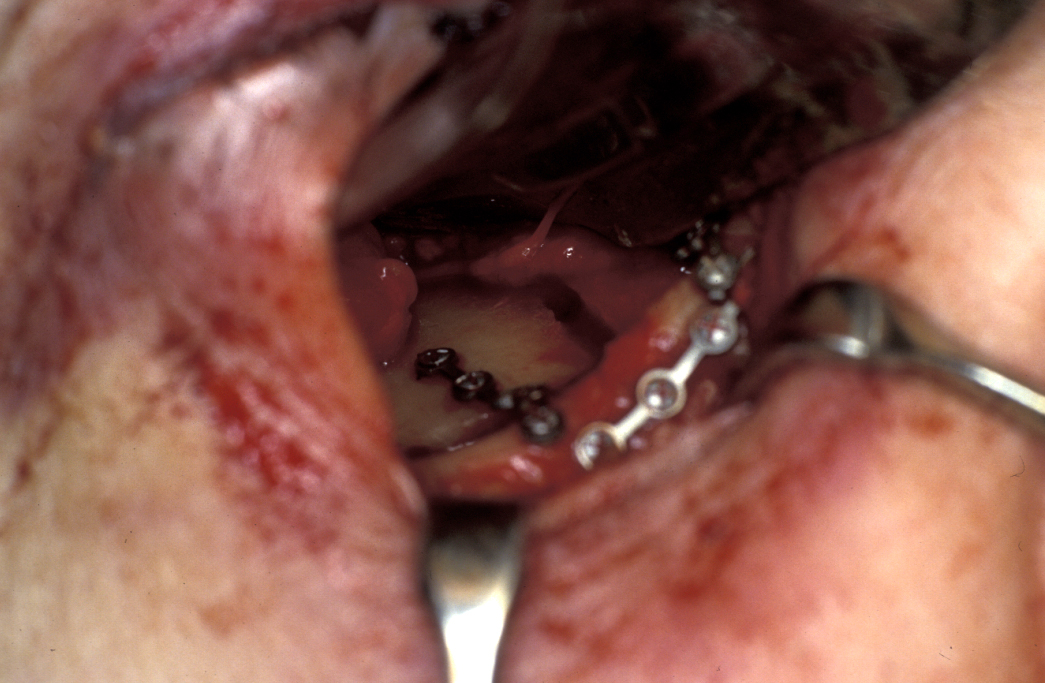

Definitive surgery usually involves open reduction and internal fixation (ORIF) under general anaesthesia, ideally using nasoendotracheal intubation. This allows the patient’s mouth to be closed and the teeth to be manipulated into their normal occlusion. This manipulation helps reduce the mandible into the prefracture bone position. Temporary intermaxillary fixation (IMF) is applied using a variety of techniques (trainee’s hand, eyelets, transalveolar screws (see Figure 1 and Figure 2), ‘rapid IMF’, arch bars). This helps to hold the fracture in its reduced position. Placing a bridle wire or tension band around the teeth can help reduce and temporarily fix the fracture.

Under direct vision via buccal sulcus incisions (incision in the depression between cheek and arch of jaw) the mandibular fracture is exposed and reduction confirmed (see Figure 3).